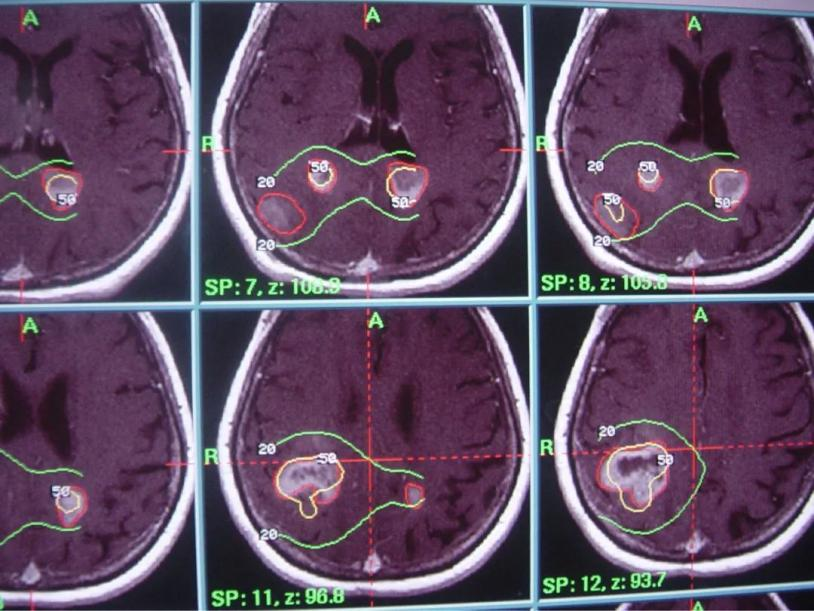

2) 病灶影像定位(MRI或者CT下)

3) 计划设计与审核

伽马刀又称立体定向伽马射线放射治疗,是融立体定向技术和放射技术于一体,以治疗颅内疾病为主的立体定向放射外科治疗设备。其原理是将钴-60发出的伽马射线几何聚焦,集中射于病灶,一次性致死性的摧毁靶点内的组织,射线经过人体正常组织几乎无伤害,并且剂量锐减,相比其他治疗照射范围与正常组织间界限非常明显,边缘如刀割一样,人们形象称之为“伽玛刀”。

2. 采用旋转聚焦的手段,可以做到靶区剂量高,而周围正常组织受量较低,保护了正常的脑组织;